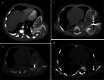

Materials and methods: We collected data of children with thoracic mesenchymal hamartomas who were treated at our institution from 2005 to 2020 using various percutaneous techniques. Techniques included radiofrequency thermoablation, microwave thermoablation (microwave thermoablation) and cryoablation.

Results: Five children were treated for chest wall hamartomas; one child showed bilateral localization of the mass. Two children underwent microwave thermoablation, one radiofrequency thermoablation and two cryoablation; one child treated with cryoablation also had radiofrequency thermoablation because mass volume increased after the cryoablation procedure. The median reduction of tumor volume was 69.6% (24.0-96.5%). One child treated with microwave thermoablation showed volumetric increase of the mass and underwent surgical removal of the tumor. No major complication was reported.